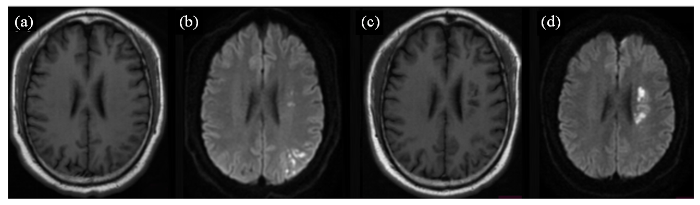

一位多发急性脑梗塞复发患者磁共振轴位SE T1WI (a、c)、DWI (b、d)图像. 患者首次住院,行磁共振检查显示,左侧放射冠区和左侧顶叶区多个急性梗塞病灶,呈长T1信号(a),DWI弥散受限呈高信号(b);患者康复出院后6个月出现临床症状,行磁共振检查显示,左侧放射冠区多个急性梗塞病灶,呈长T1信号,左侧放射冠区见多个软化灶(c),DWI扩散受限呈高信号(d)

Fig. 1

Magnetic resonance axial SE T1WI (Fig. a, c) and DWI (Fig. b, d) of a patient with recurrent multiple acute cerebral infarcts. The patient was admitted to the hospital for the first time, and an MRI showed multiple acute infarction lesions in the left radiocaudate region and the left parietal lobe, with long T1 signals (Fig. a) and high DWI signals indicative of restricted diffusion (Fig. b). The patient developed clinical symptoms six months after discharge from rehabilitation, an MRI showed multiple acute infarction lesions in the left radiocaudate region with long T1 signals and multiple areas of infarction were also seen in the left radiocaudate region (Fig. c); diffusion-limited DWI with a high signal (Fig. d)